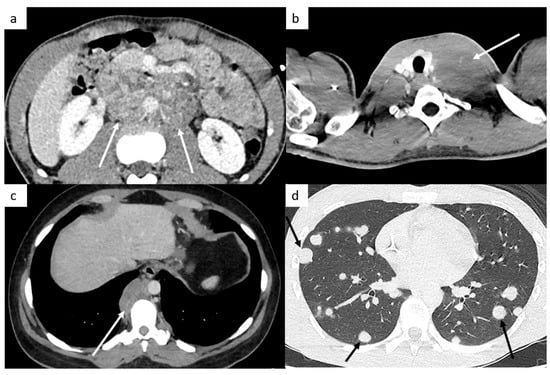

The retroperitoneal lymph nodes are the most common sites for TGCT (Figure 1). CT imaging remains the standard modality used for assessment of lymph node involvement, distinguishing between stages II (retroperitoneal nodes considered as regional lymph nodes) and III (supra-diaphragmatic nodes considered as metastatic disease) [21].

Figure 1.

Most common sites of lymph nodes and metastases in testicular cancer. Abdominal computed tomography (CT) shows retroperitoneal paraaortic lymph nodes (a, arrow). Thoracic CT reveals left supraclavicular lymph node (b, arrow). Thoracic CT demonstrates posterior mediastinal lymph nodes (c). Thoracic CT scan shows lung metastases appearing as multiple lung nodules (d).

The M stage defines the presence of distant metastatic disease, including distant lymph nodes outside the retroperitoneum. TGCT can spread above the diaphragm to the posterior mediastinum via the thoracic duct, it is therefore very important to analyze this region (Figure 1). NSGCT have a more random spread involving the anterior mediastinum, aortopulmonary window, hilar, supraclavicular and neck lymph nodes [33].

This M stage is most often present in choriocarcinoma and yolk sac tumors because of their hematogenous dissemination. The most common metastatic site of solid organs is the lungs. Most of the time, lung metastases appear as multiple lung nodules (Figure 1).